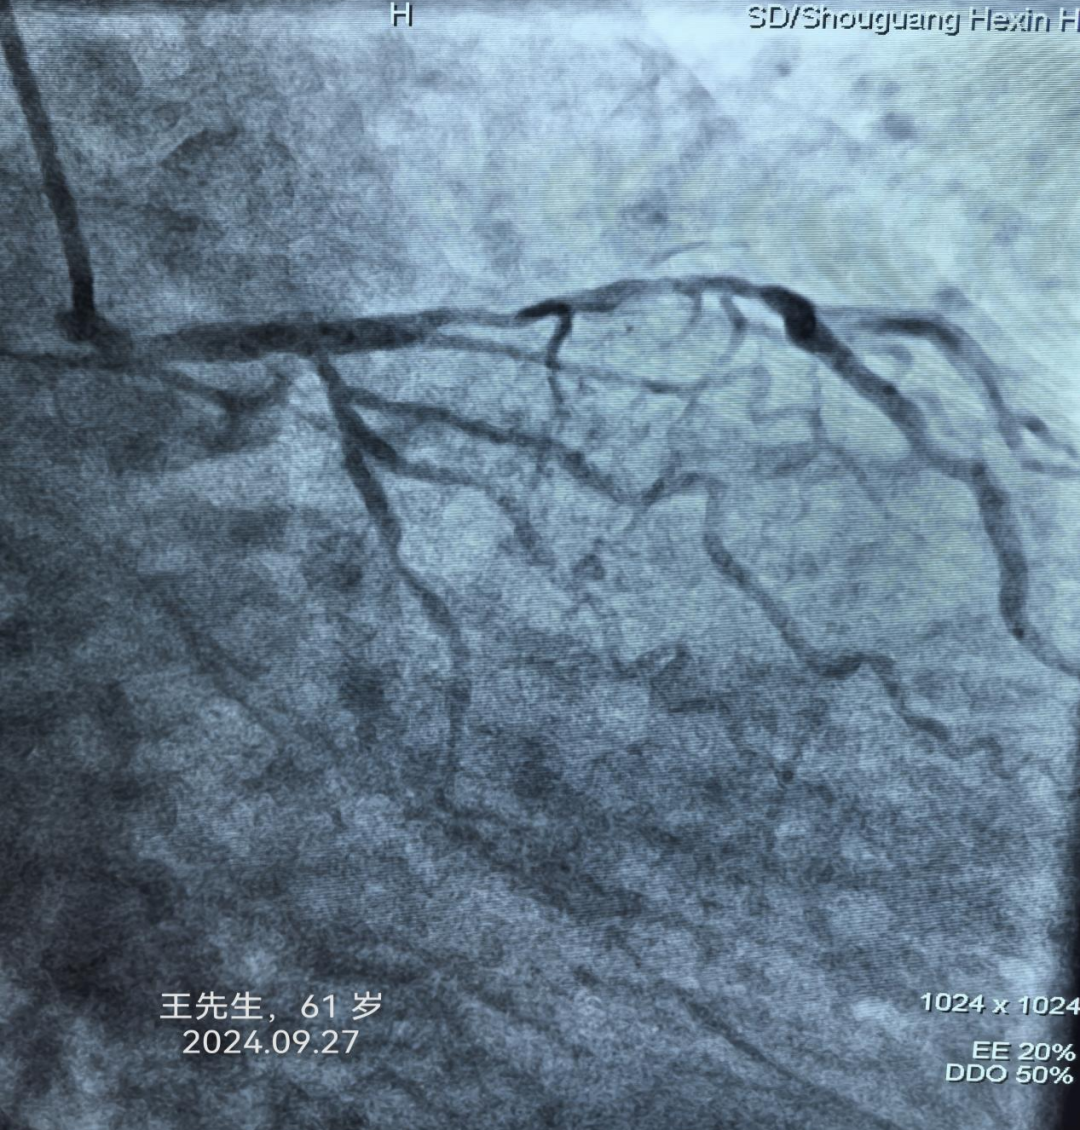

病例1:王先生,61岁,诊断“不稳定型心绞痛”。

寿光和信医院目前引进的中国联影640排高端螺旋CT天河960+,对冠脉成像有独特的优势,可无限制心脏成像,单心跳-高心率冠脉成像、单心跳-严重心律不齐、单心跳-自由呼吸扫描,成像效果极佳,与冠脉造影结果差距极小,并且检查时间3-5分钟、较之前缩短75%。部分冠脉CTA、冠脉造影结果对比如下: